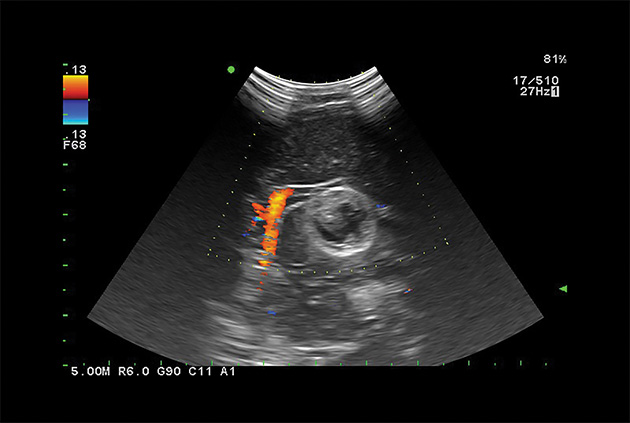

Dual CF

Real-time side-by-side display of a B-mode image and Color Doppler image assisting in easy anatomical interpretation of blood flow.